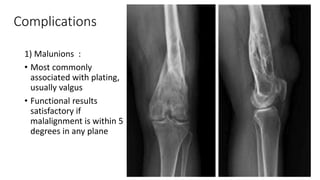

1) Malunions :

• Most commonly

associated with plating,

usually valgus

• Functional results

satisfactory if

malalignment is within 5

degrees in any plane

Complications 1) Malunions : •Most commonly associated with plating, usually valgus • Functional results satisfactory if malalignment is within 5 degrees in any plane